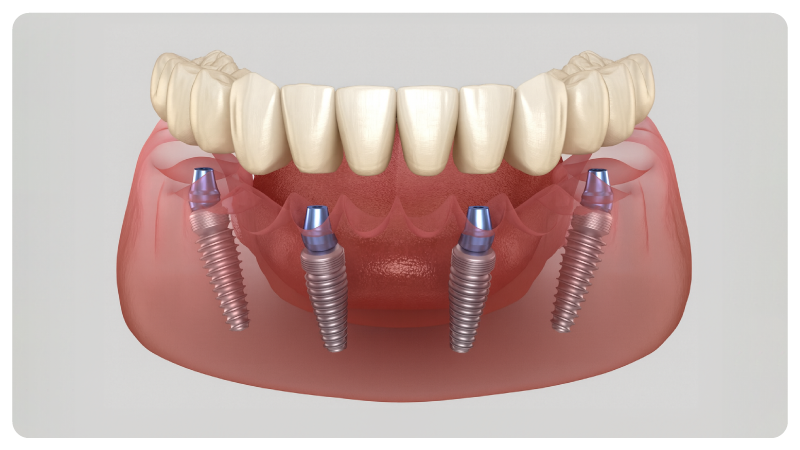

All On Four:

Dientes Fijos en un Solo Día

La técnica All On Four permite recuperar una sonrisa completa con 4 implantes estratégicamente colocados, sobre los que se fija una prótesis permanente para restaurar estética y funcionalidad.